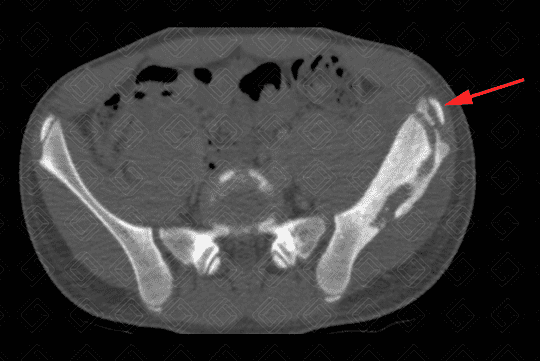

Texto alternativo para a imagem Figuras 1, 2 e 3. Créditos: Dra. Elazir Mota - Rio de Janeiro/RJ

Descrição das figuras 1, 2 e 3: Tomografia computadorizada de bacia, após a administração do contraste venoso. Paciente do sexo masculino, 13 anos, evidenciando extensa área de esclerose na asa do ilíaco esquerdo, com áreas líticas de permeio (setas vermelhas). Na janela de partes moles, observa-se aumento de partes moles e coleção adjacente à lesão óssea descrita (asterisco).